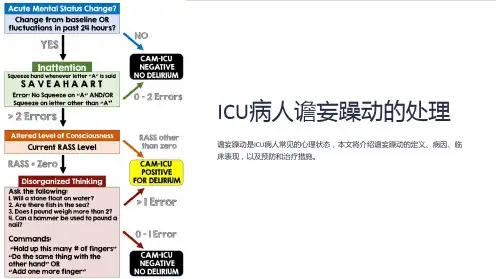

如何诊断谵妄?谵妄的诊断主要依据临床检查及病史,ICU中常使用ICU患者意识模糊评估法(CAM-ICU量表)对患者进行谵妄评估。

谵妄的评估分为两步:第一步:使用Richmond镇静-躁动评分(RASS)对患者的意识/镇静水平进行评;第二步:使用CAM-ICU从①意识状态的波动②注意缺损③意识清晰度④思维紊乱4个方面进行评估。

如同时出现①和②,再出现③和(或)④即可诊断谵妄。